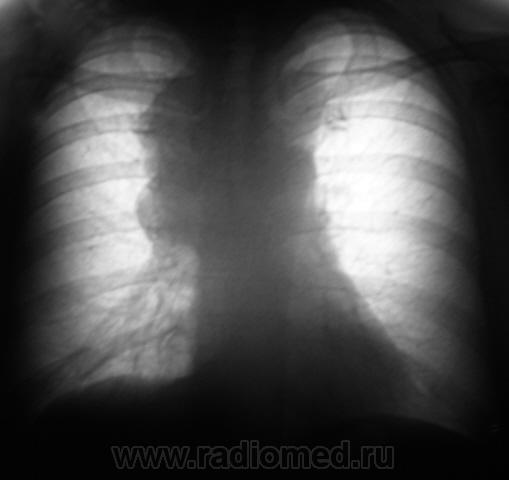

Флюорограмма, ровно через год.

Пациент "взят на контроль".